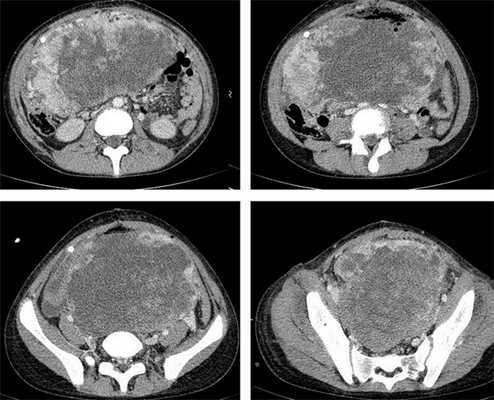

Рисунок 8. КТ органов брюшной полости - на снимках вы можете увидеть опухоль яичника.

Компьютерная томография органов грудной клетки, брюшной полости, малого таза используются для оценки распространения опухолевого процесса (рис.5).